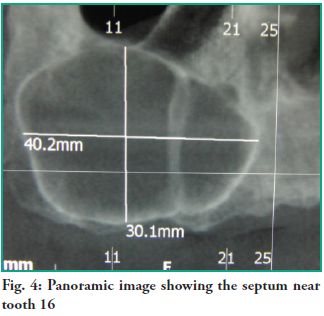

A computerized tomography (CT) scan is indicated for diagnostic purposes and to design a treatment plan. Images were obtained using single cone-beam x-ray CT and corroborated that the lesion measured 40.2 mm in the anterior-posterior direction by 30.1 mm in the vertical direction. All tomographic slices show that the right maxillary sinus is occupied by a lesion with septation near tooth 13, which has not deformed the nasal wall of the maxillary sinus (Figs. 4 and 5).

A computerized tomography (CT) scan is indicated for diagnostic purposes and to design a treatment plan. Images were obtained using single cone-beam x-ray CT and corroborated that the lesion measured 40.2 mm in the anterior-posterior direction by 30.1 mm in the vertical direction. All tomographic slices show that the right maxillary sinus is occupied by a lesion with septation near tooth 13, which has not deformed the nasal wall of the maxillary sinus (Figs. 4 and 5).